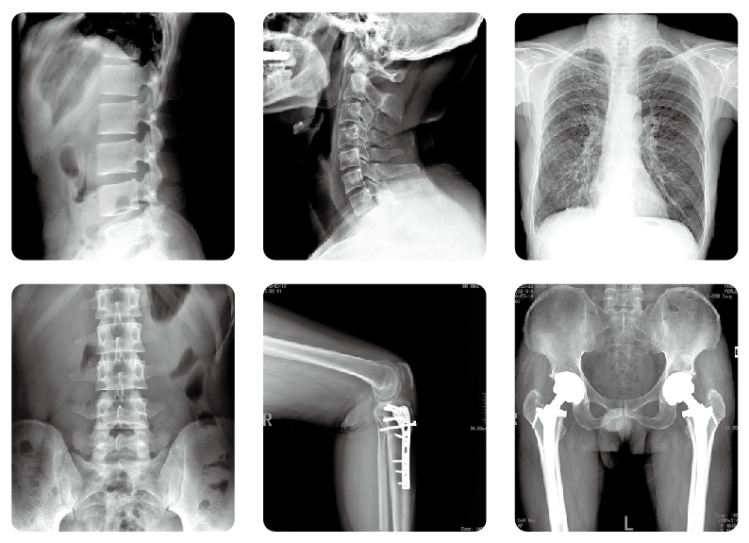

放射科拍片

拍攝一張普通X光胸片,其曝光率約為0.045mSv/S。拍攝一張胸部肋骨大約需要0.5S,因此接受一次胸部X線檢查,患者需要承受0.023mSv的輻射量。根據(jù)國際放射委員會制定的標準,輻射總危險度為0.0165/Sv,也就是說,身體每接受一西弗特(1Sv=1000mSv)的輻射劑量,就會增加0.0165的致癌率,以此推算,一張胸片會增加約為千萬分之零點六的危險。對其他醫(yī)學檢查來說,四肢約為0.01mSv,腹部為0.154mSv,骨盆為0.66mSv,腰椎為1.4mSv,上消化道為2.55mSv。因此單次醫(yī)學檢查導致健康人群患癌的風險在千萬分之一到十萬分之一之間。

放射科DR設備

況且,現(xiàn)在各大醫(yī)院均已全面采用DR設備,輻射劑量較普通X線照片大幅減少,常規(guī)放射檢查的劑量更在安全范圍內(nèi)。所以,除特殊個體(如懷孕早期)外,我們普通人一般不需要考慮輻射損傷的問題,完全可以安心就診。